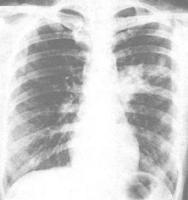

呼吸系統解剖圖?發病急劇有高熱咳嗽痰多及胸痛胸痛紫紺氣急心悸約半數患者有畏寒等症狀臨床表現類似因為的肺炎球菌肺炎但其痰常呈粘稠膿性量多帶血灰綠色或轉紅色膠凍狀但此類典型的痰液並不多見若病變累及胸膜或心包可引起滲出性或膿性積液病灶的纖維組織增生活躍易於機化纖維素性胸膜炎可早期發生粘連胸部X線表現常呈多樣性包括大葉實變好發於右肺上葉雙肺下葉有多發性蜂窩狀肺膿腫葉間隙下墜確診克雷白桿菌肺炎疾病可進行血常規X線細菌學等檢查可通過抗生素(紅黴素左氧氟沙星)等藥物進行治療或頭孢菌素聯合氨基糖苷類抗生素如頭孢噻肟鈉或頭孢他啶靜滴合併阿米卡星或妥布黴素肌注或靜滴亦可選擇哌拉西林鈉(氧哌嗪青黴素)與氨基糖苷糖聯用部分病例使用氟喹諾酮類氯黴素等亦有效克雷白桿菌肺炎的預後較差病死率高

肺炎克雷白桿菌常存在於人體上呼吸道及腸道,當機體抵抗力降低時,經呼吸道進入肺內引起大葉子或者小葉融合性病變,以上葉為多見。病灶中滲出液粘稠而重,致使中間隙下墜。細菌具有莢膜,在肺泡內生長繁殖時,引起組織壞死、液化、形成耽擱或多發性膿腫。若病變累及胸膜或心包,可引起滲出性或醫|學教育網蒐集整理膿性積液病灶的纖維組織增生活躍,易於機化,纖維素性胸膜炎可早期發生粘連。